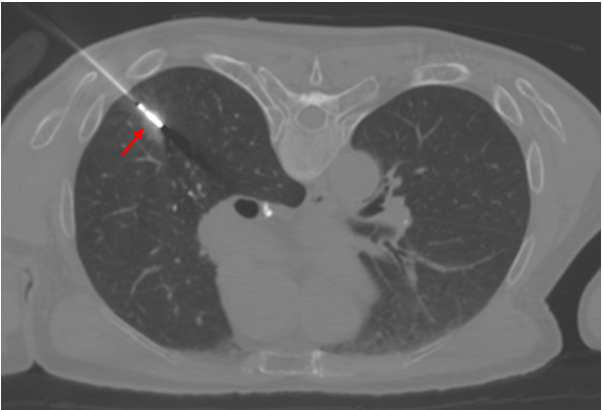

微创消融,精准消灭肺结节

根据老唐的情况,为其制定了经皮穿刺活检同步微波消融的诊治方案。通俗地说,就是局部麻醉后,在CT引导下采用同轴套管针(直径1.2mm)经皮精准穿刺肺结节,拔除针芯后,建立一个体表至肺结节的通路,再将活检枪经这个通路穿刺至肺结节获取组织病理。同样可以将微波消融针经这个通路穿刺至肺结节进行消融治疗,使其发生凝固性坏死。

△患者术中采用俯卧位,CT引导下经皮穿刺活检同步微波消融